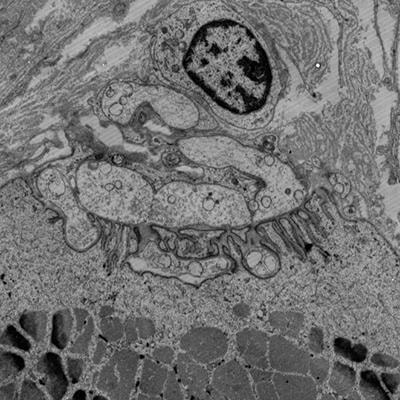

Myasthenia gravis (MG) is a rare autoimmune disease, hallmarked by pathogenic autoantibodies targeting the neuromuscular junction (NMJ). The antibodies affect AChR densities and neuromuscular architecture, which impairs neuromuscular transmission and causes the cardinal symptom of fatigable muscle weakness that can be life-threatening if respiratory muscles are affected. MG is a heterogeneous disease with diverging age of onset, disease severity, treatment responses, thymic pathologies, and autoantibody constellations.